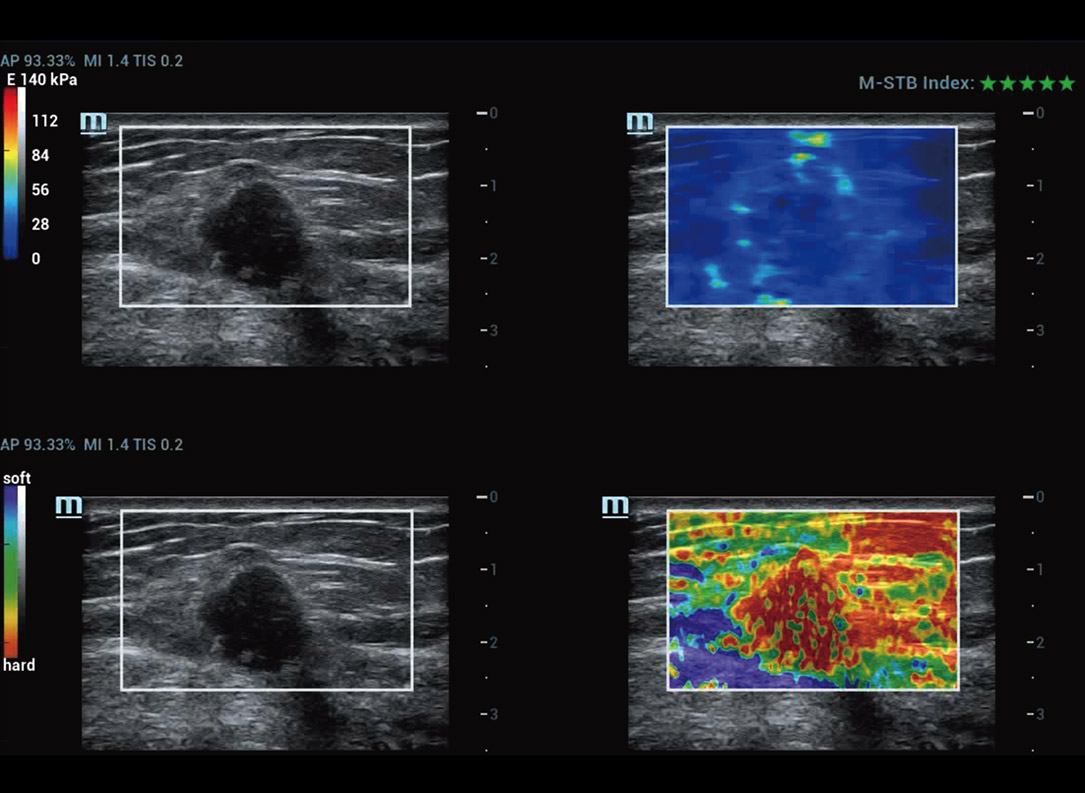

Strumenti di analisi multiparametrica M-Reference

M-Ref. E Compare

M-Ref. E Compare tumore maligno al seno

M-Ref. E Compare supporta la visualizzazione dell'elastografia strain in tempo reale e della STE in un unico piano per la valutazione della rigiditĂ dei tessuti.

Elastografia Strain

- SensibilitĂ , produttivitĂ , penetrazione e precisione elevate

- Un unico "involucro" per l'analisi dell'area di infiltrazione del tumore

Elastografia Strain